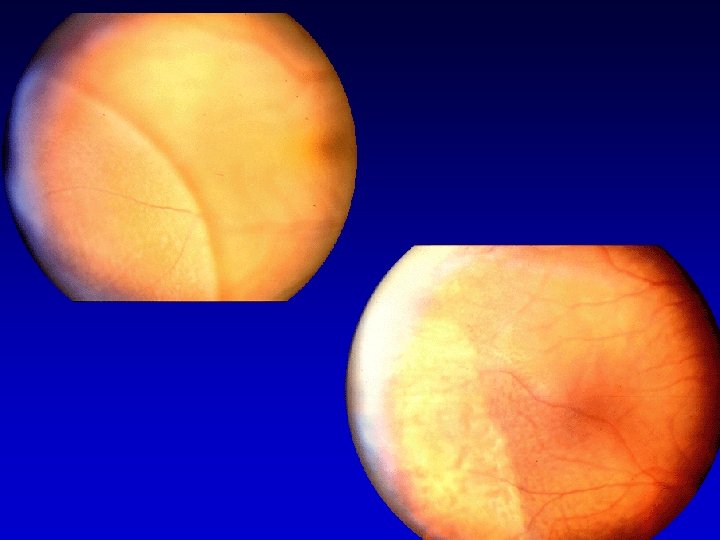

TRATTAMENTO CHIRURGICO SCOPI : • Occlusione della rottura • Detensione delle trazioni • Drenaggio del liquido sottoretinico • Appianamento della retina • Pessia della rottura TECNICHE : • AB ESTERNO • AB INTERNO

CHIRURGIA AB ESTERNO Tempi operatori Peritotomia congiuntivale Peritotomiacongiuntivale Isolamento dei muscoli retti Apposizione dicerchiaggio in bandelletta di silicone cerchiaggioin bandellettadi larga 2. 5 mm e spessa 0. 5 mm e/opiombaggi in piombaggiin silicone rigido o spugna in silicone Fissazione delcerchiaggio mediante due punti in cerchiaggiomediante mersilene 5/0 per quadrante mersilene 5/0 Annodamento delcerchiaggio con piccolo anello di cerchiaggiocon silicone Drenaggio del liquido sottoretinico Sutura della congiuntiva invicryl 8/0 Pessia ? ( crio ? laser ? )

CHIRURGIA AB INTERNO Tempi operatori Apertura della congiuntiva e della sclera a 3. 5 -4 mm dal limbus Vitrectomia centrale e periferica Segmentazione delle membrane epiretiniche e talvolta sottoretiniche Immisione di sostanze reintegranti o tamponanti quali: Bss , aria, miscele di gas espansibili (sf 6, c 3 f 8, etc. . ) olio di silicone, doppio tampone Endodiatermia, fotocoagulazioine Sutura della sclera in vicryl 7/0 , della congiuntiva in vicryl 8/0